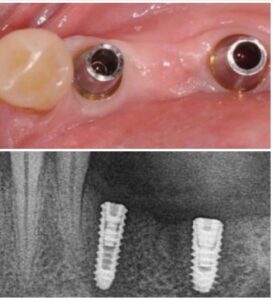

تقنيات حديثة للزراعة

تضيف اجهزه البانوراما الداخلية واجهزة التصوير ثلاثية الأبعاد بعدًا آخر لتقنية الزرع من خلال صورها الدقيقة للفك والأسنان. هذه الدقة ضرورية لتخطيط ووضع الغرسات. يوفر تقييمًا دقيقًا للبنى التشريحيه مثل الأعصاب وجذور الأسنان والجيوب الفكية ومعرفة طبيعة العظم وكثافة وما إلى ذلك ، مما يمنع أي احتمال للفشل الذي يحدث بسبب التشخيص الخاطئ. تم تجهيز مراكز الزرع لدينا بهذه الآلات المتطورة ، مما يمكننا من تنفيذ كل حالة من حالات الزرع بدقه عاليه وأعلى درجات النجاح.